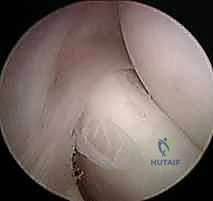

* يتم استئصال النسيج الندبي والتنكسي الرمادي اللون بدقة متناهية (Excision of angiofibroblastic tissue).

* تقشير العظم (Decortication): يقوم الدكتور هطيف بعمل ثقوب دقيقة جداً في عظم اللقيمة الوحشية. هذا الإجراء الحيوي يسمح بخروج الخلايا الجذعية وعوامل النمو من نخاع العظم إلى منطقة الوتر، مما يحفز بناء نسيج وتري جديد وقوي.

2. جراحة الكوع بالمنظار (Arthroscopic Tennis Elbow Release)

باعتباره رائداً في جراحة مناظير المفاصل في اليمن، يقدم الدكتور هطيف خيار الجراحة بالمنظار (بتقنية 4K عالية الدقة).